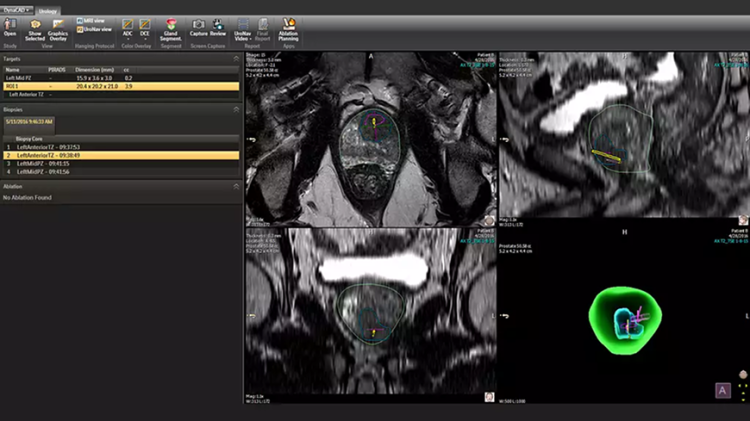

DynaCAD 泌尿外科与放射学中使用的 DynaCAD Prostate 配合使用,为泌尿科医生提供一种存储、审查和管理综合诊断和治疗数据的简单方法。它提供了专门用于泌尿科检查的查看布局和工具。

放射科使用 DynaCAD Prostate 定义前列腺边界和目标后,DynaCAD 泌尿科会显示结果信息以供泌尿科检查。专用工具允许您根据需要编辑前列腺分割,并根据先前的活检程序核心位置添加目标。这为使用飞利浦 UroNav 的融合引导活检创建了一个即用型计划。